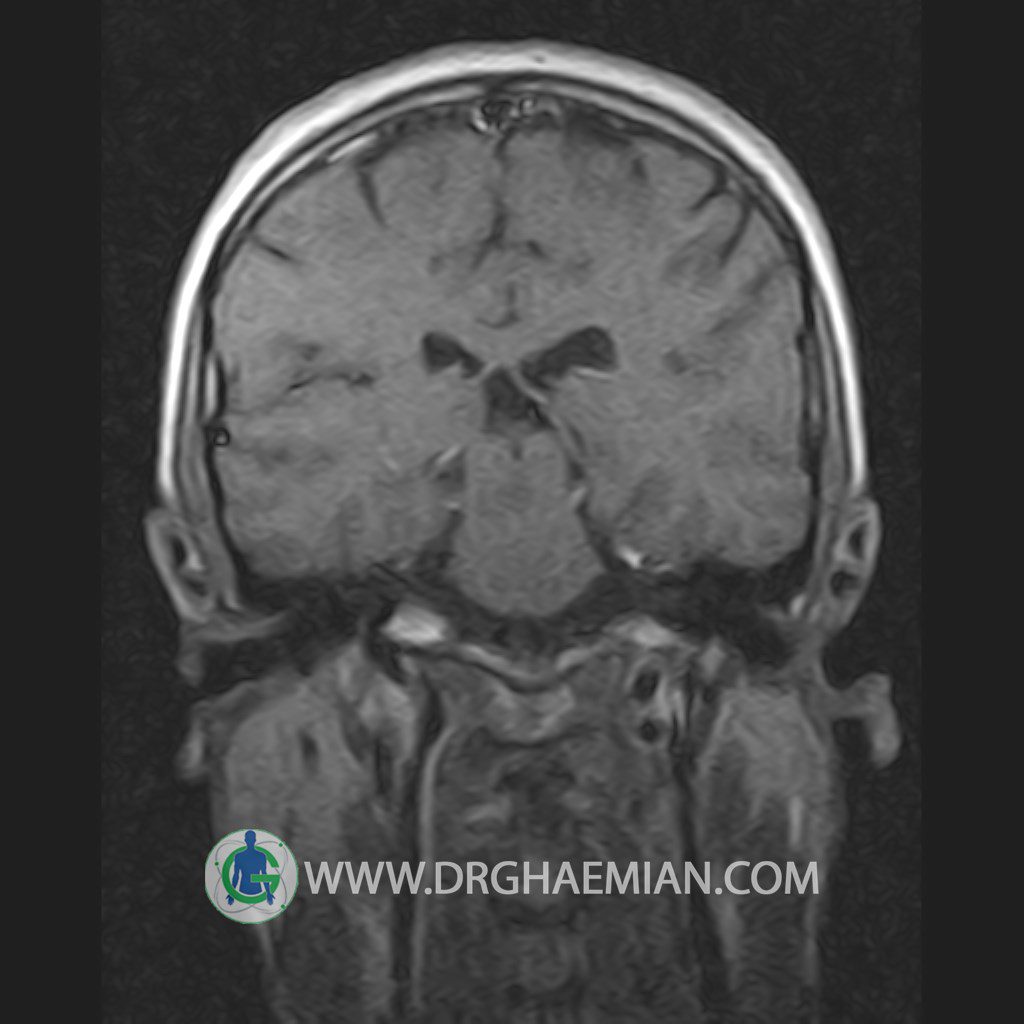

پزشکان اغلب از تصویربرداری ام آر آی برای تشخیص و درمان عارضه های پزشکی که فقط با استفاده از اشعه ایکس یا میدان مغناطیسی و امواج رادیویی قابل مشاهده است، استفاده می کنند. دستگاه ام آر آی تصاویر دقیق از ساختار های داخلی بدن ایجاد می کند. در این کیس یک میکروآدنوم در هیپوفیز بیمار مشاهده می شود.

HYPOPHYSIS MRI

(with and without contrast)

Technique: Axial , coronal T1 , Axial , coronal , sagittal T2 , Axial, coronal T1 post Gd & 64 dynamic thin coronal slices.

REPORT :

The infundibulum is centered and of normal size .

The optic chiasm and suprasellar spaces appear normal .

The cavernous sinus and imaged portions of the internal carotid artery and carotid siphon are unremarkable .

Evaluable portions of the neurocranium show no abnormalities .

The sphenoid sinus is clear and pneumatized .

Imaging of the hypothalamus after contrast medium administration was normal.

– Small hypoenhancing mass lesion ( 3 x 4 mm ) in posterior of pituitary stalk suggestive for micro adenoma

– Mucosal thickening in ethmoid & maxillary sinuses

is seen